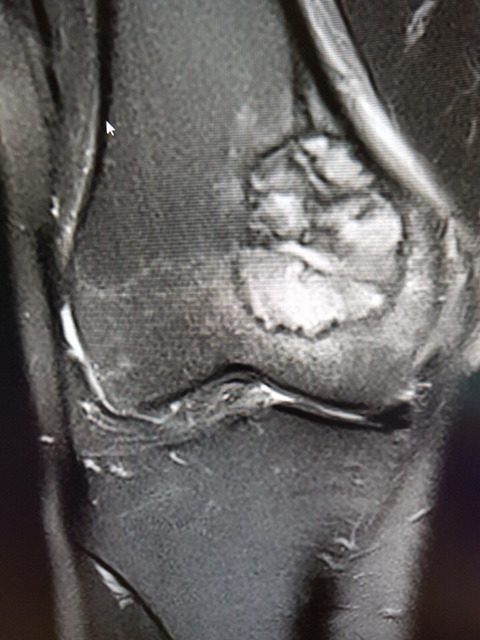

무릎 거대세포종

6월부터 통증있다가 8월말 mri 찍고 삼성의료원 방문하여 조직검사 후에 9.13 거대세포종 판정 받았습니다.

수술은 10.5 예정이고, 교수님께서 골 소파술 이후 골시멘트로 채울 계획이고, 관절은 안건드린다고 하셨습니다.

크기는 지름 3.5cm

• 작성자소중한분 작성자 본인 여부 작성자 | 작성시간 18.10.09 댓글 첨부 이미지 이미지 확대